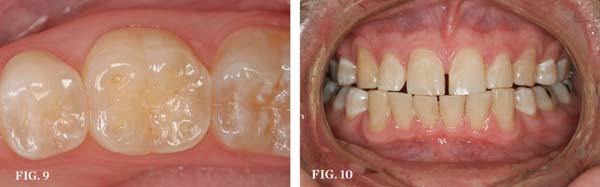

The teeth themselves often can be full of diagnostic information. Is there excessive tooth wear (Figure 7 through Figure 9)? Is there excessive mobility in any teeth? Is there unwanted migration of teeth? Is there a centric relation/maximum intercuspation discrepancy (hit on inclines and slide into full intercuspation) (Figure 3)? If there is a discrepancy, is the deviation in the arc of closure or line of closure? Is the patient able to chew all types of food on both sides without pain? Does the patient feel like their bite is changing or unstable? In addition, are there functional patterns evident by the wear present on the teeth. For instance, horizontal bruxers (Figure 10) often have flat tabletop wear present. Vertical, constricted wear patterns (Figure 11) often have anterior chipping and lingual wear of maxillary anterior teeth.

CLINICAL EXAMPLES (9.) Posterior dentinal exposure is a sign of occlusal instability; this exposure will only get worse if the cause is not resolved and the tooth restored. (10.) An example of a horizontal functioning patient; note the flat “table-top” wear patterns.

Figure 9  CLINICAL EXAMPLES Posterior dentinal exposure is a sign of occlusal instability; this exposure will only get worse if the cause is not resolved and the tooth restored.

Figure 9

Figure 10  CLINICAL EXAMPLES An example of a horizontal functioning patient; note the flat "table-top" wear patterns.

Figure 10